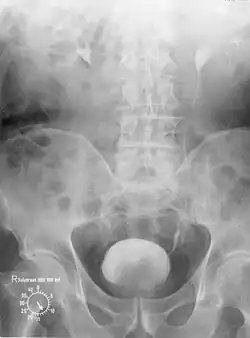

Wilhelm Conrad Röntgen entdeckte 1895 die nach ihm benannten Röntgenstrahlen. Damit begann die Entwicklung der Radiologie. Was die Urologie betrifft, wurde 1906 erstmals die von Friedrich Voelcker und Alexander von Lichtenberg entwickelte „retrograde Pyelographie“ vorgestellt, wobei das Nierenbeckenkelchsystem und die Harnleiter mit einer Kollargol-Lösung dargestellt wurden. Es kam dabei jedoch zu schwersten Nebenwirkungen.[53] 1927 wurden von Maurice Chevassu Harnleiter und Nierenbecken mit Kontrastmittel, das im Rahmen einer Blasenspiegelung direkt in die Harnleitermündung eingebracht wird, dargestellt.[54] 1929 führte von Lichtenberg die Pyelographie, d. h. die Darstellung der ableitenden Harnwege über in die Vene eingebrachtes Kontrastmittel, wieder in die Diagnostik ein. Am 28. September 1929 wurden auf dem 9. Deutschen Urologen-Kongress in München von Alexander von Lichtenberg und Moses Swick[55][56] erstmals die Fachwelt überzeugende Urogramme (mittels des durch die Chemiker Arthur Binz und Curt Räth entdeckten Uroselectan)[57] und damit erstmals brauchbare Röntgenbilder der Niere demonstriert.[58][59] Damit waren neue Wege der Diagnostik eröffnet.[60] Die Röntgenfotografie wurde bei einer Nierensteinoperation erstmals von dem Nürnberger Urologen Eduard Pflaumer durchgeführt.[61] Die 1973 eingeführte axiale Computertomographie ermöglichte auch in der Urologie weitere Verbesserungen.